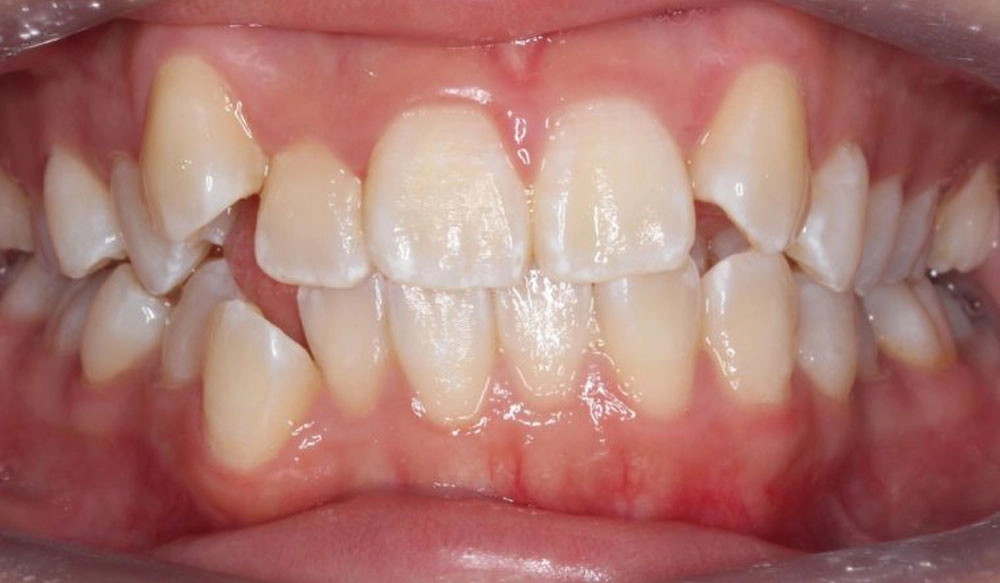

Class III

Class III — or “underbite” — is the condition in which the mesiobuccal cusp of the upper first molar is positioned distally to the mesiobuccal groove of the lower first molar instead of both being aligned, affecting the occlusal relationship between both dental arches.

Patient Information:

Age: 27

Gender: Female

Invisalign Treatment Option: Invisalign Comprehensive

Total Treatment Time:

28 months